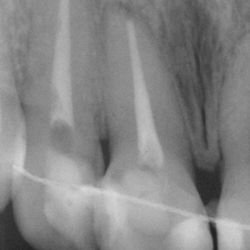

This young patient had completed an orthodontic treatment which had led to pulp necrosis in her upper right central and lateral incisor.

The teeth were root-treated and as a result, they were discolored.

We re-enforced the strength of these teeth using aesthetic fiber posts and restored their shade with nanotechnology composite resin veneers.